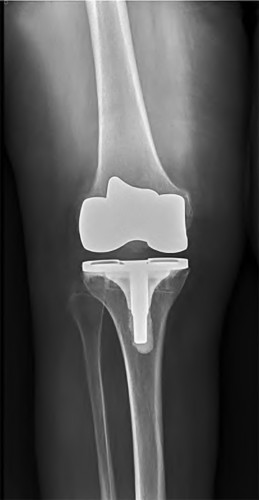

During a revision total knee arthroplasty, removal of the tibial component reveals a massive contained metaphyseal defect measuring 3 cm deep, but with an intact cortical rim. According to the Anderson Orthopaedic Research Institute (AORI) classification, what type of defect is this, and what is the preferred method of management?